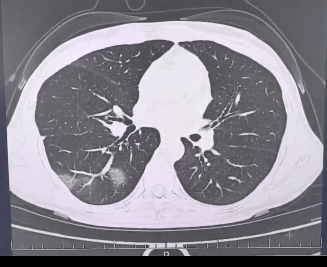

检查结果显示,

程女士的好几叶肺

都出现了“白肺”现象,

指间血氧饱和度只有 88%,

血心肌酶谱、肌钙蛋白的指标、肝功能的指标

也出现了明显的异常。

确诊流感(重型)!

图源:杭州市第三人民医院微信公众号